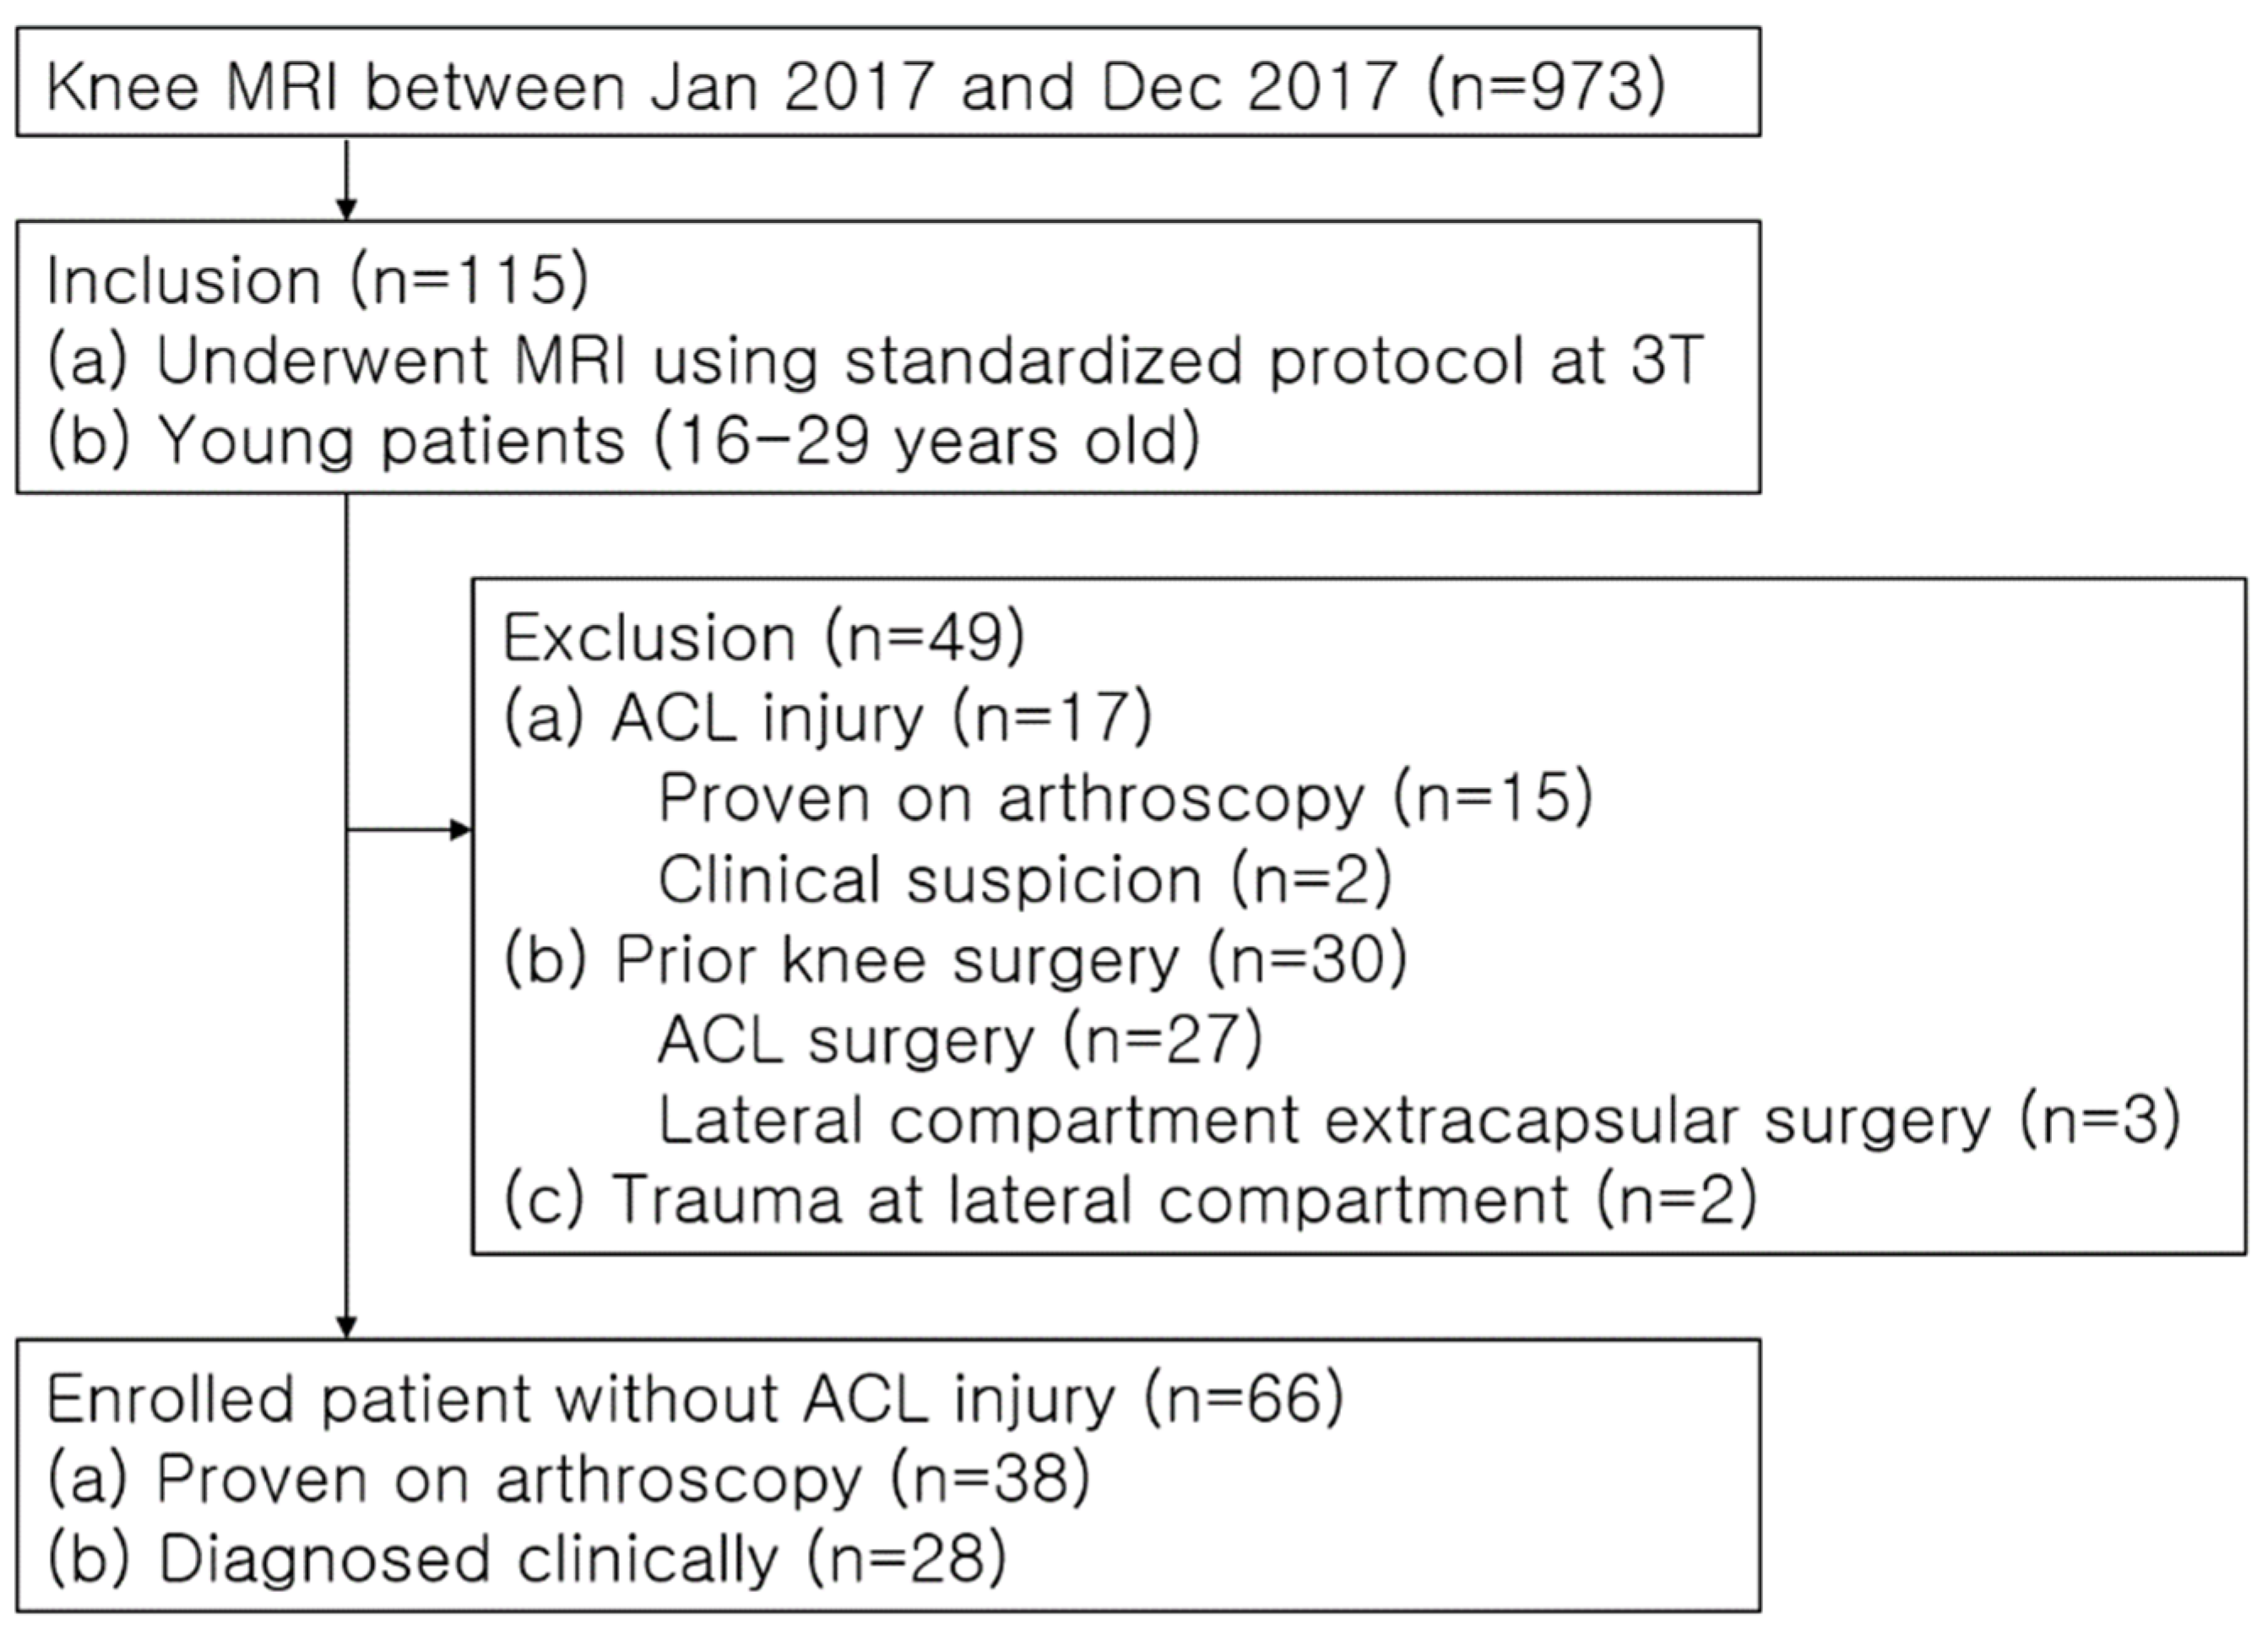

2.1. Study Population